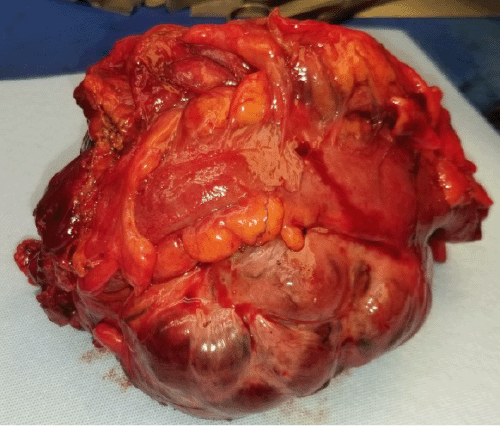

Pathology revealed a 15 × 13 × 10 cm predominantly circumscribed mass with focally infiltrative margins (Figure 2). Histologic assessment of the tumor revealed areas of infarct-like necrosis and hemorrhage. The tumor was composed of cells with indistinct to delicate borders without gland formation with ovoid, grooved nuclei sometimes growing in a distinctive lace-like pattern (Figure 3). The tumor cells had a low mitotic rate without atypical mitosis. Immunohistochemistry was positive for inhibin-alpha, S100, actin, SF1, and pan-cytokeratin with retained INI-1 expression, indicating that the tumor was an adult granulosa cell tumor (GCT). Cytogenetics was negative for abnormalities.

Figure 2. Gross Surgical Specimen of Adult Granulosa Cell Tumor. Published with Permission

Figure 3. Histologic Section From Tumor Mass. Published with Permission